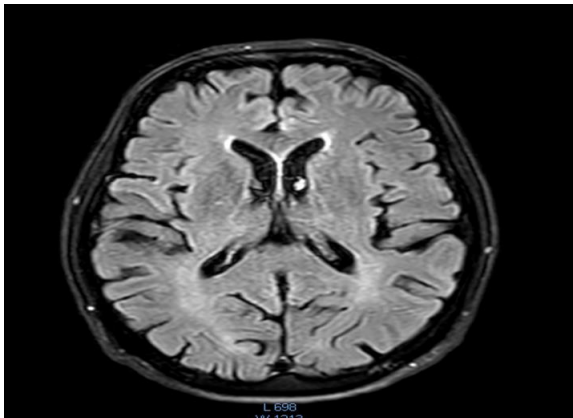

In our patient, who has examined, all the symptoms in detail, it can be said that he had most of these symptoms. Although the main key to the disease is gait and balance disorders and limping, speech problems, especially stuttering in certain languages, as well as pronunciation of difficult words or non-native languages, along with a significant decrease in muscle strength and swallowing problems, were more obvious than the other symptoms. However, no significant damage was seen in terms of vision problems or psychological.problems, as well as short-term or long-term memory. MMSE test =27 Especially since he can concentrate on a single subject for hours and even do significant research. The latest MRI of the brain, taken at the end of 2024, is attached and shows that no lesions are visible. (2)

Fig 1